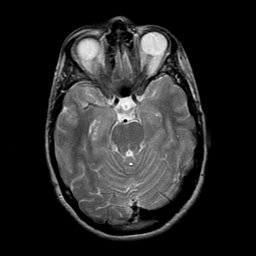

overlay -- Slice #9

[Home][Help][Clinical] Slice 9